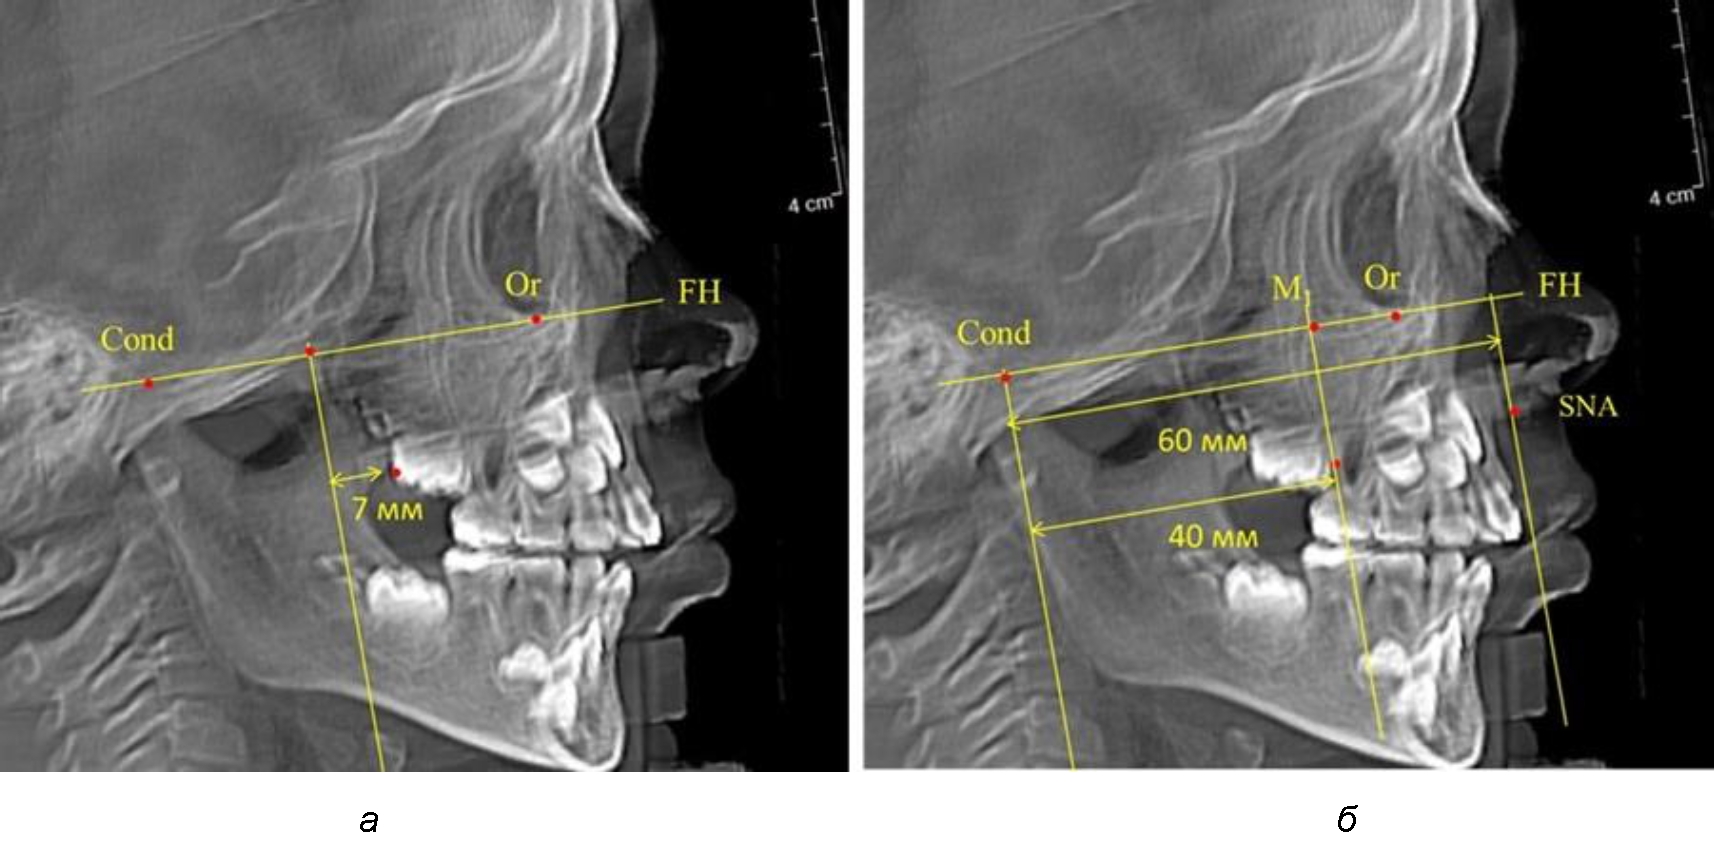

При проведении анализа к Франкфуртской горизонтали проводили передний и задний перпендикуляры. Передний спинальный перпендикуляр проходил через выступающую точку передней носовой ости (spina nasalis anterior – SNA), а задний суставной перпендикуляр опускали из кондилярной точки Cond. Молярный перпендикуляр проводили через медиальную поверхность первого постоянного моляра. Указанная вертикаль отделяла замещающие зубы постоянного прикуса от добавочных зубов (постоянных моляров), что вполне логично для анализа положения первых постоянных моляров в гнатическом комплексе (рис. 1).

Рис. 1. Метод определения положения первых верхних моляров по Ralph E. McDonald (а) и по предложенному методу (б)

Так, при расстоянии от крыловидной вертикальной плоскости PTV до дистальной поверхности верхнего первого постоянного моляра в 13 мм сагиттальный размер гнатического отдела был 82 мм. При этом отношение кондилярно-спинального расстояния к кондилярно-молярному размеру (54,5) было близким к коэффициенту 1,5, что представлено на рис. 2.

Рис. 2. Особенности положения первых моляров по R. E. McDonald (а) и по предложенному методу (б) при уменьшенном молярно-крыловидном расстоянии